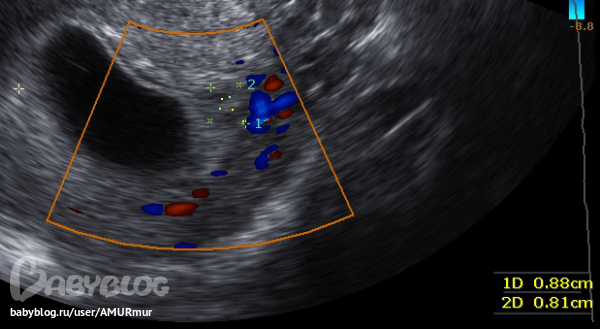

Сижу как на иголках два часа, ищу на бб подтверждение, что мазня темно-красная, это вовсе не мазня))) Ну правда испугалась. В общем, накрутила я себя ужасно. У директора отпросилась на "снимок пазух носа" (а что? я же еще с секретиком в животе, а про насморк и не соврала, была бы не беременная, может и правда отправилибы на снимок, а так - нате мазь, мажьте) и в 15:00 улетела на платное узи. Добралась быстро и уже в 15:40 нас с малявочкой смотрели. Хотя сначала все выспросили - какие выделения, что болит и пр., а потом посмотрели окружение плода. Итог исследования: в области внутреннего зева ретрохориальная гематома 8х8мм.

Она и дала мазню, которой кстати сейчас и след простыл, но может вновь появится, поэтому - "Не пугайся, не волнуйся, угроз выкидыша нет, все закрыто, а гематома или рассосется сама собой или выйдет тем же небольшим безболезненным кровотечением"